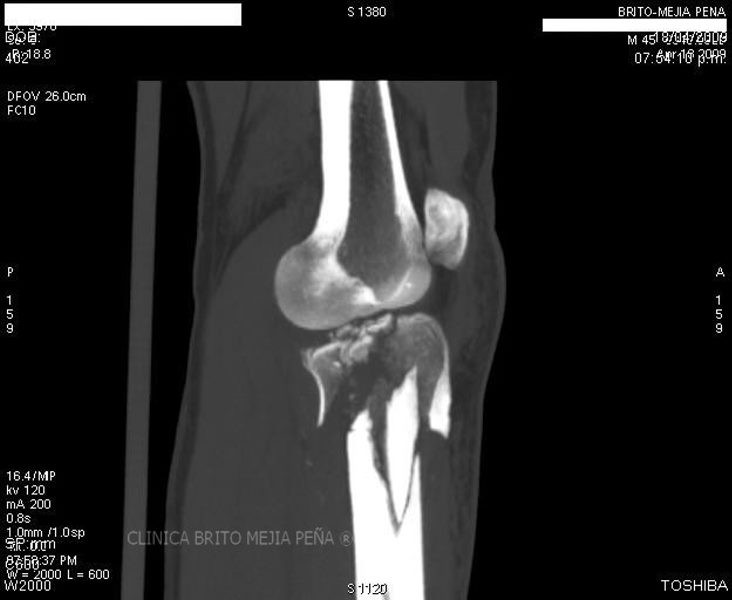

Fractura tibia MPR

Post Image